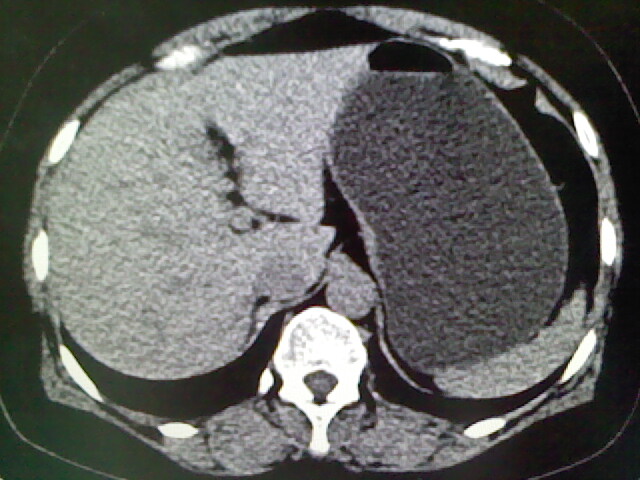

以下是引用卜一在2009-4-2 13:26:00的发言:[br]胆囊颈部结石伴胆囊炎!另:建议增强,待除外肝内占位及胆囊占位!

以下是引用liaoqiang在2009-4-2 16:23:00的发言:[br]胆囊是否切除?胆囊颈区致密影考虑金属夹?结石?肝脏右叶低密度影,考虑增强。